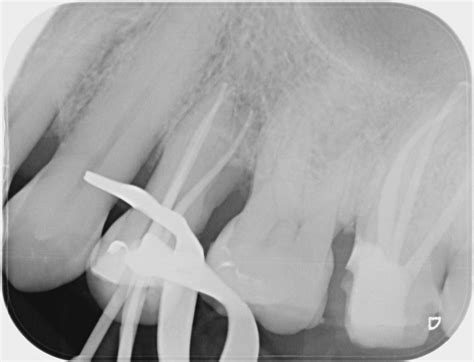

1. Diagnosis and Anesthesia: Using digital X-rays, the professional locates the infection. Local anesthesia is administered to ensure the patient is comfortable throughout.

• rct molar xray